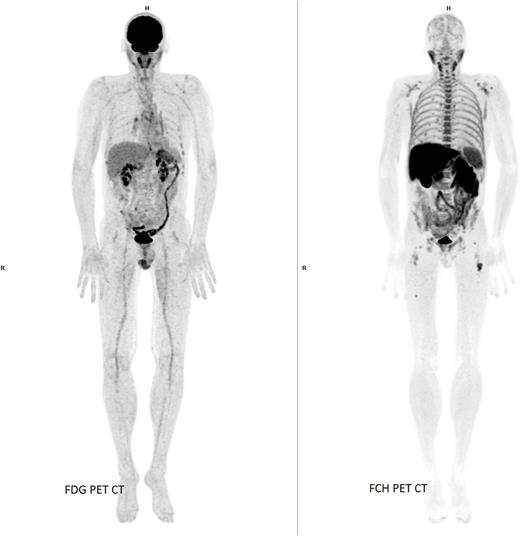

Introduction: Hybrid positron emission tomography/computed tomography (PET/CT) has now become available, as well as whole body, low dose multi-detector row computed tomography (MDCT) or magnetic resonance imaging (MRI). The usefulness of 18F-fluorodeoxyglucose (FDG) PET/CT in evaluating multiple myeloma (MM) has been proven for several years but its sensitivity is imperfect. In a pilot study, we showed that 18F-fluorocholine (FCH) could have some advantages compared to FDG in suspected relapsing or progressive MM, since it is able to pinpoint lesions with a less intense metabolism and/or located in the skull, which are not revealed by FDG. The aim of the present study was to compare the diagnostic performance of PET/CT using FCH and FDG, in various settings of MM: staging, follow-up or suspected relapse.

Results: The 77 patients (average age = 67.3 year old) underwent 95 couples of FDG and FCH PET/CTs, all within 30 days: 17 for staging, 45 for follow-up (some patients had iterative PET/CTs) and 33 for suspected relapse. Among the 45 follow-up PET/CTs, 13 were intended purely to monitor treatment. No foci were found in 41 PET/CTs (6 for staging, 22 for follow-up and 13 for suspected relapse). Uncountable foci were observed in 10 cases with both tracers, but mismatched FDG/FCH foci in 1 case. Concerning countable foci, in 5 staging PET/CTs FDG showed 21 foci vs. 22 FCH foci, in 18 follow-up PET/CTs 32 FDG foci vs. 41 FCH foci, in 14 cases of suspected relapse 26 FDG foci vs. 55 FCH foci (+53%). Median SUVmax and T/NT was overall greater for FCH than for FDG, significantly in case of suspected relapse. There was no significant difference for median SUVmax and T/NT between FDG and FCH PET/CTs performed for staging. Of the 7 cases of diffuse bone marrow infiltration, 2 were better detected with FDG and 5 with FCH. Extramedullary spread was detected in 2 patients, foci of similar intensity being visible with both tracers. In all PET/CTs monitoring treatment for efficacy evaluation, FCH showed as reliable results as did FDG. FCH had better specificity than FDG, without some misleading foci of FDG in cases of inflammation (two cases), brown fat (one case) or post-traumatic fracture (one case). In 3 patients, the management decided on basis of FDG PET/CT was changed in view of FCH PET/CT.

Conclusions: These findings suggest that FCH PET/CT could have a role in all settings of MM, in particular in case of suspected relapse or progression, because it would reveal more lesions than FDG and avoid some pitfalls. Further investigations are needed to determine significance of mismatched FDG and FCH foci, and in which patients it is worthwhile to complete the exploration with FCH, or whether using FCH instead of FDG would lead to detrimental decisions in some patients.